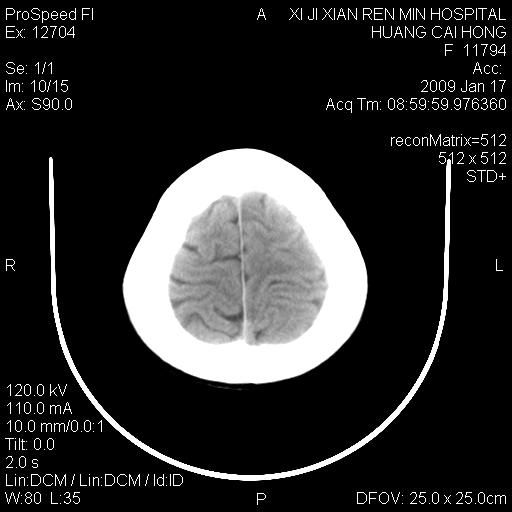

以下是引用zbp537在2009-1-19 13:54:00的发言:[br]首先考虑脑炎。[br]诊断依据:[br]1、患者较年轻。[br]2、有感冒病史。[br]3、左侧颞枕叶这么大一片低密度影,占位征象却不明显,不符合肿瘤特征,其内的高密度影为出血灶。

以下是引用xiaoniu在2009-1-19 13:29:00的发言:[br]左侧颞叶三角形低密度影,占位效应不明显,其内点片样高密都影,青少年患者,首先考虑:少突胶质瘤。因为有感冒病史,不能除外感染的可能。